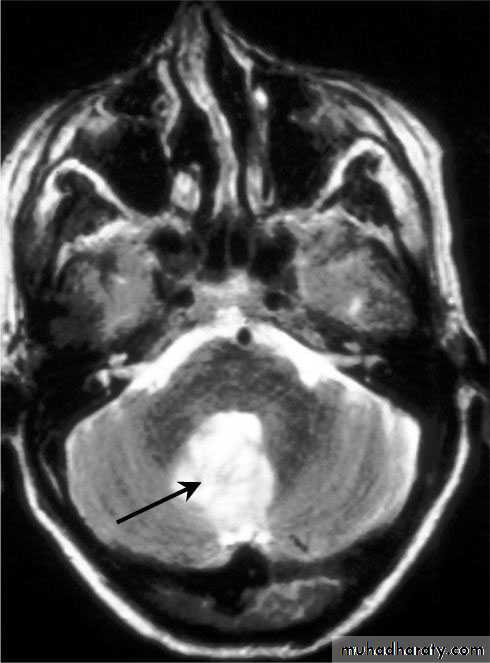

Cerebellar Abscess

• Cerebellar Abscesses.